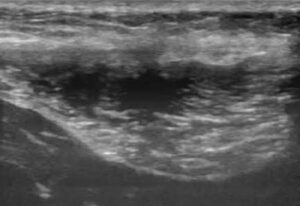

- 28/06 ecografia = lesione muscolare di 3° grado

Mentre nel sano si evidenziano le fibre muscolari ipoecogene frammiste al perimisio ecogeno, nel malato si vede l’area anecogena, un vero e proprio buco: le miofibrille sono strappate. Attorno all’area anecogena un alone iperecogeno, rappresenta l’infiammazione. È presente anche una notevole atrofia muscolare.

Controllo ecografico 11/08

• lesioni compatibili con strappo parziale del muscolo gracile

• rispetto a precedente eco lesione ridotta, 1/3 spessore musc vs 90%

• nessun segno di fibrosi

Controllo ecografico 18/10

• rispetto a precedente controllo la lesione è stabile come dimensioni

• non evidenti fenomeni fibrotici e no segni di infiammazione acuta